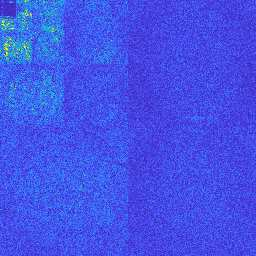

Magnetic Resonance Imaging (MRI) has excellent soft tissue contrast but is hindered by an inherently slow data acquisition process. Compressed sensing, which reconstructs sparse signals from incoherently sampled data, has been widely applied to accelerate MRI acquisitions. Compressed sensing MRI requires one or more model parameters to be tuned, which is usually done by hand, giving sub-optimal tuning in general. To address this issue, we build on previous work by the authors on the single-coil Variable Density Approximate Message Passing (VDAMP) algorithm, extending the framework to multiple receiver coils to propose the Parallel VDAMP (P-VDAMP) algorithm. For Bernoulli random variable density sampling, P-VDAMP obeys a "state evolution", where the intermediate per-iteration image estimate is distributed according to the ground truth corrupted by a zero-mean Gaussian vector with approximately known covariance. To our knowledge, P-VDAMP is the first algorithm for multi-coil MRI data that obeys a state evolution with accurately tracked parameters. We leverage state evolution to automatically tune sparse parameters on-the-fly with Stein's Unbiased Risk Estimate (SURE). P-VDAMP is evaluated on brain, knee and angiogram datasets and compared with four variants of the Fast Iterative Shrinkage-Thresholding algorithm (FISTA), including two tuning-free variants from the literature. The proposed method is found to have a similar reconstruction quality and time to convergence as FISTA with an optimally tuned sparse weighting and offers substantial robustness and reconstruction quality improvements over competing tuning-free methods.